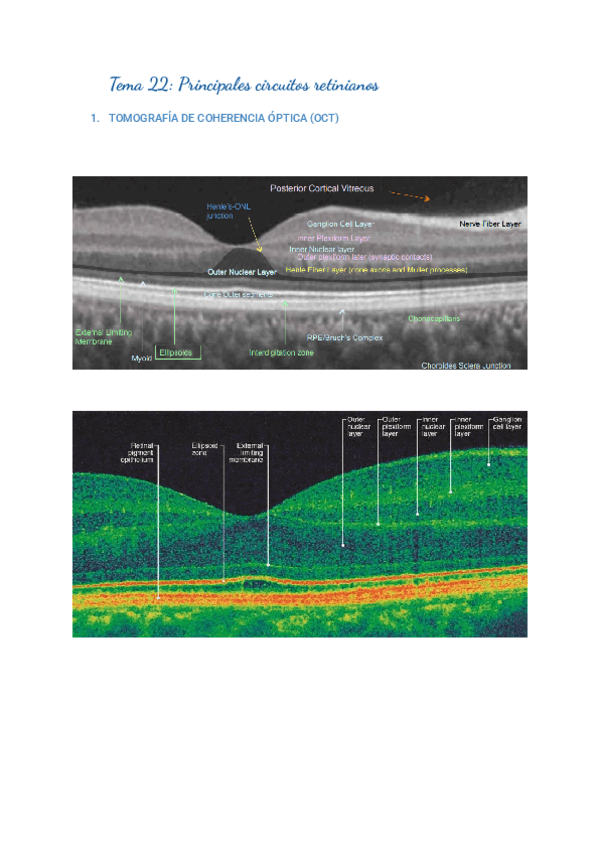

Tema-22-Principales-circuitos-retinianos.pdf